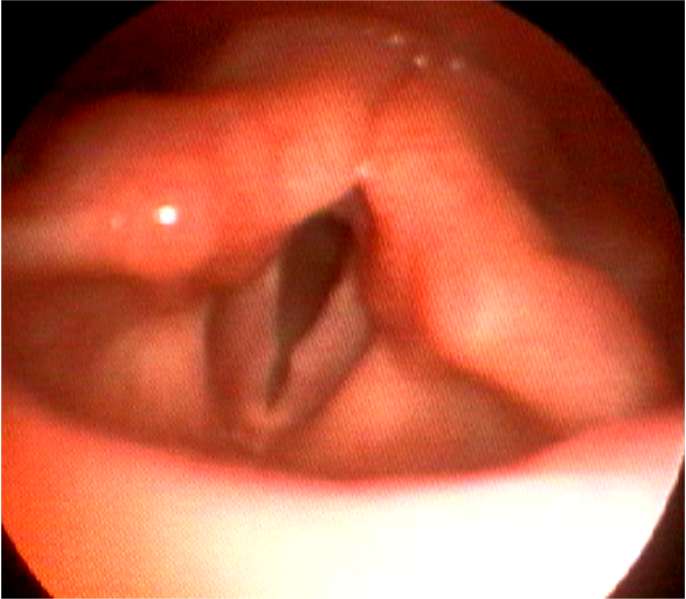

・声帯ポリープは声帯結節、声帯ポリープ、ポリープ様声帯の3種類にわけられます。

・声帯ポリープは成人の男女にみられ、通常、片側性で声を酷使する職業の人に発生します。